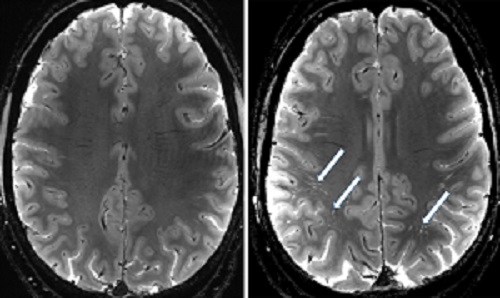

By building a registry of patients who experienced traumatic brain injury, the team can track individuals over time and see the changes in the brain from its early stages. “One of the most surprising findings is how quickly we are seeing changes in the brain after a head injury. The perivascular spaces that make up the glymphatic system enlarge rapidly, sometimes within hours of injury. This may help the brain eliminate harmful waste products. But in people who have experienced multiple head injuries, this response seems to be diminished.”